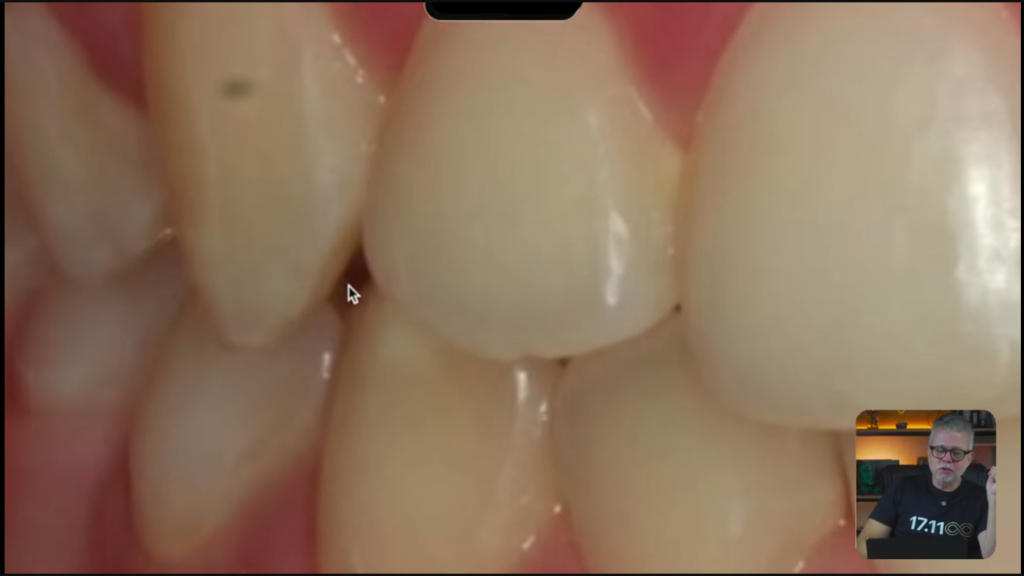

Alguns detalhes como, vejam que parece que tem um espaço escurecido aqui no incisivo lateral:

Por que ficou assim, professor?

Anatomia do dente.

Hélio, o que mais que tem de problema?

Olha o zênite desse lateral e olha desse lateral aqui: